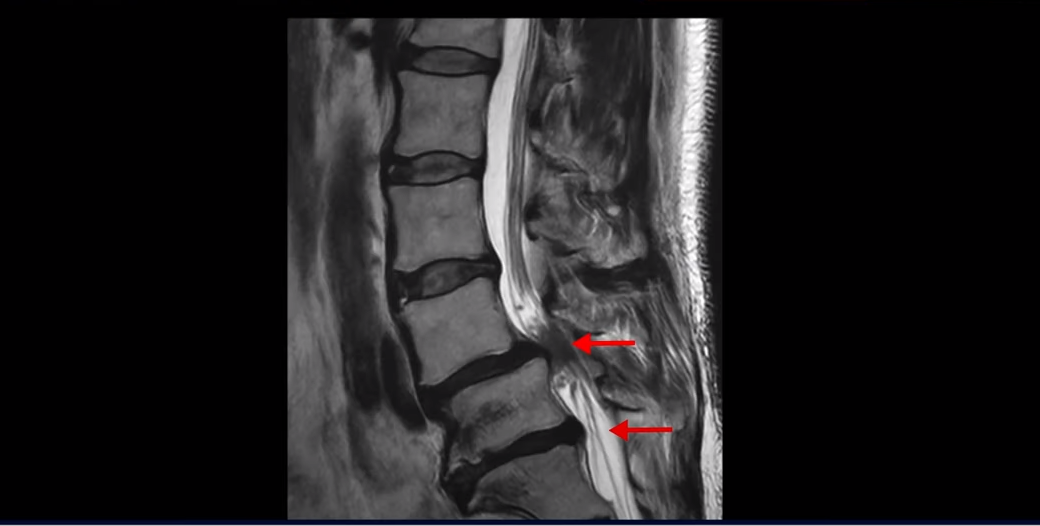

제가 먼저 이 환자분 MRI를 보면서 설명 드린 후 이분 말씀 더 들어보겠습니다. 보시다시피 두 마디가 심하게 퇴행되어 있고

4번 5번에는 척추뼈가 밀려나간 전방전위증이 있습니다.

4번 5번에 심한 중심성 협착도 있습니다.

양쪽 신경 가지가 빠져 나가는 추간공도 왼쪽 오른쪽 모두 좁아져 있습니다.

5번 1번에는 가운데로는 디스크가 밀려나와 있습니다.

이건 아주 오래된 퇴행성디스크로 보입니다. 그래서 이 환자분은 양쪽 엉덩이와 다리가 모두 저리고 아픈 게 양쪽 추간공 문제 때문일 수도 있고 중심성 협착 때문일 수도 있습니다. 퇴행성디스크 때문에 아플 가능성은 상대적으로 적어보입니다.